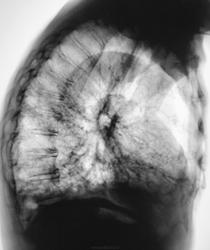

Это конечно шутка, а на самом деле здесь пневмония на фоне порока развития правого легкого. Справа внизу множественные ячейки. Ну и последствия травмы справа. Пневмония, думаю - дело временное.

Типа «сотовое лёгкое»? Нет? интересно, как оно выглядело до болезни?

Томограммы.

Диф Ds поликистоз

бронхоэктазы

пневмосклероз с развитем сотового лёгкого?

Пневмония (возможно грибковая)

Я никак не могу разглядеть просвет среднедолевого бронха, проходим ли он в должной степени? Очень интересно было бы посмотреть контроль